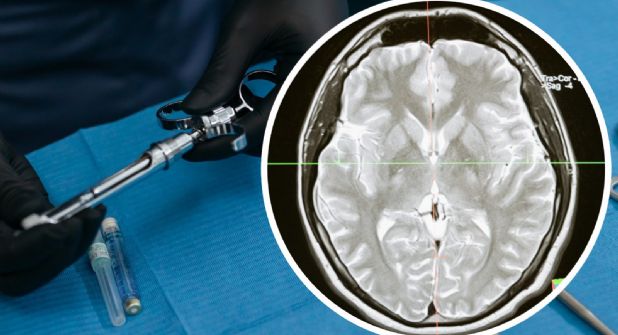

¿Qué es la meningitis fúngica?

De acuerdo con información de esta dependencia, es una enfermedad que se caracteriza por la inflamación de las meninges, una capa que recubre el cerebro. Se desarrolla tras contraer una infección de hongos. Esta enfermedad ocurre cuando la infección se traslada desde otra parte del cuerpo como los pulmones, al cerebro o la médula espinal.

Las personas que sufren esta infección pueden experimentar fiebre, dolor de cabeza, rigidez de cuello, náuseas, vómito, fotofobia y confusión.